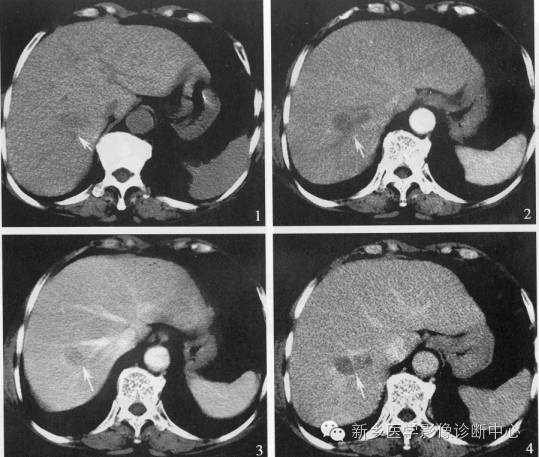

16、肝脓肿

肝脓肿可由溶组织阿米巴原虫或细菌感染所引起。阿米巴肝脓肿的发病与阿米巴结肠炎有密切关系,且脓肿大多数为单发;细菌性肝脓肿的细菌侵入途径除败血症外,可由腹腔内感染直接蔓延所引起,亦可因脐部感染经脐血管,门静脉而入肝脏,胆道蛔虫亦可为引起细菌性肝脓肿的诱因。常见的细菌有金黄色葡萄球菌,链球菌等。此外,在开放性肝埙伤时,细菌可随致伤异物或从创口直接侵入引起肝脓肿;

肝脓肿的病理改变为肝组织局部充血、水肿、蜂窝织炎,继而坏死、液化形成脓腔。脓肿壁由炎症充血带或纤维肉芽组织形成。

肝脓肿的典型CT 表现为:

a)肝内低密度占位,边缘多模糊,内可见分隔及气体;

b)增强后低密度病灶周边可见环形强化,可以是单环、双环和三环。单环为脓肿壁,双环代表脓肿壁(内环)和周围水肿带(外环),三环则表示除外环水肿带外,脓肿壁有内外两层构成,外层(中环)一般为纤维肉芽组织,强化最明显,内层(内环)由炎症组织构成;

c)增强后脓肿内分隔强化,呈“簇状征”:是指肝内呈蜂窝状的小低密度脓肿;

d)“肝段强化”征:是指动态增强扫描动脉期脓肿旁的一过性强化。

e)胆源性肝脓肿的特征性改变为:脓肿与扩张的胆管相通或紧邻、胆系积气、胆系结石。